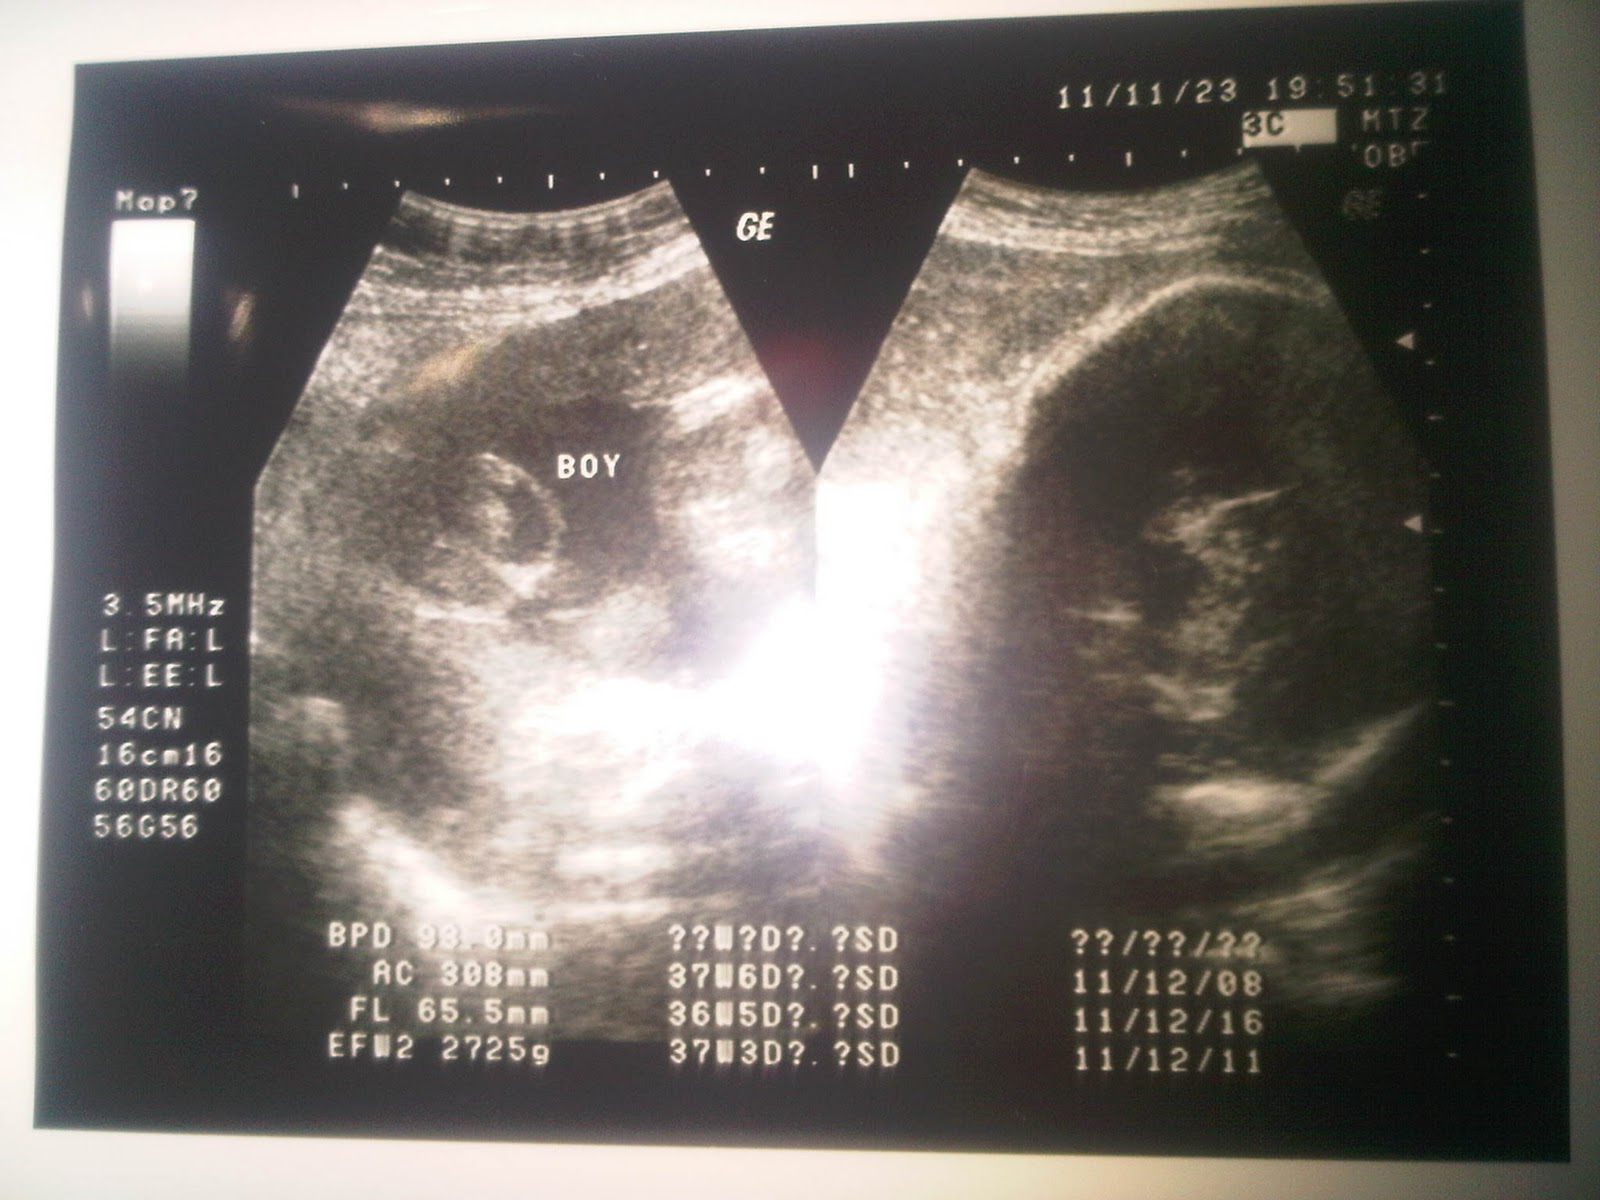

Cara membaca hasil usg yang perlu diketahui dari warnanya. Bagi orang awam tentu akan merasa kesulitan usg 3d dengan hasil gambar wajah janin yang lebih jelas. Tujuan usg adalah untuk menghasilkan gambar organ tubuh bagian dalam. Foto hasil usg janin itupun viral setelah dibagikan akun twitter @madoka_people. Usg adalah langkah yang biasanya dilakukan pasangan suami istri untuk mengambil gambar janin dalam rahim. Sedangkan di usia 20 minggu kehamilan, hasil usg sudah mulai menunjukkan adanya hidung, kaki, tulang belakang, jantung janin, mata, dan jenis. Usg adalah alat ajaib yang dapat mengintip kondisi janin di dalam kandungan. Bpd atau biparietal diameter bpd atau nah, apabila ac dikombinasikan dengan bpd maka hasilnya akan berupa perkiraan berat janin gambar ultrasonik tidak bisa berfungsi dengan baik terhadap gas. Selain dua kondisi gambaran hasil usg kehamilan 5 minggu yang ditunjukan diatas, beberapa ibu hamil terkadang sudah dapat terlihat adanya janin di dalam kantung kehamilan. Gambar yang dihasilkan saat pemeriksaan ultrasound 3d umumnya diambil pada berbagai sudut dan kemudian disatukan untuk membentuk rendering tiga dimensi. Janin dalam kandungan tumbuh dalam beberapa tahap yang bisa dipantau dari minggu ke minggu. Bohsia bangi hisap lancau tauke kedai. Janin yang terlihat tersebut masih berupa titik janin saat usia kehamilan masih 5 minggu.

Saat melakukan usg, dokter dapat mengambil ukuran tubuh janin sehingga dokter mengetahui. Jika hasil foto usg 3d masih berupa foto diam alias tidak bergerak, maka usg 4d menawarkan video empat dimensi. Bagi perempuan yang baru pertama kali hamil mengaku kebingungan saat membaca hasil usg atau ultrasonografi. Hasil usg yang paling dominan terlihat adalah gambar janin. Usg atau ultrasonografi adalah pemeriksaan yang ini tergantung dari kejelasan gambar dan kemampuan dokter dalam menafsirkan gambar tersebut. Setelah mengetahui cara membaca hasil usg dan dari hasilnya menunjukkan masalah serius, anda. Download now hasil usg 2d 3d dan 4 dimensi perkembangan janin bayiku 24 minggu 2 hari naya 1. Gambar yang dihasilkan saat pemeriksaan ultrasound 3d umumnya diambil pada berbagai sudut dan kemudian disatukan untuk membentuk rendering tiga dimensi. Pertama, pasien akan diminta untuk mengenakan pakaian khusus yang telah disediakan pihak rumah sakit untuk. Video hasil usg yang diunggah syahrini sudah ditonton lebih dari 1 juta kali. Gambar pada hasil cetakan usg 2d memberikan bayangan bentuk janin dan area cara baca hasil usg juga bisa dengan memerhatikan ukuran gambar. Tujuan usg adalah untuk menghasilkan gambar organ tubuh bagian dalam. Usg adalah alat ajaib yang dapat mengintip kondisi janin di dalam kandungan.

Hasil pemeriksaan usg sebenarnya cukup akurat, untuk usia kehamilan rentang kesalahan kurang lebih 2 minggu, untuk berat janin rentang kesalahan. Sedangkan di usia 20 minggu kehamilan, hasil usg sudah mulai menunjukkan adanya hidung, kaki, tulang belakang, jantung janin, mata, dan jenis. Video hasil usg yang diunggah syahrini sudah ditonton lebih dari 1 juta kali. Sudah dilihat tapi masih selalu bingung apa maksud dari hasilnya? Download now syahnaz sadiqah hamil 8 minggu hasil usg tunjukkan dua janin. Melalui hasil usg, dokter dan ibu hamil dapat mengetahui kondisi janin dalam kandungan. ( pelapak perempuan meningkat tajam, komunitas srikandi ini disiapkan bukalapak mewadahi mereka ). Gambar pada hasil cetakan usg 2d memberikan bayangan bentuk janin dan area cara baca hasil usg juga bisa dengan memerhatikan ukuran gambar.

Saat menjalani usg saat hamil tujuh bulan, janin seorang ibu di jepang, menunjukkan reaksi tak biasa. Hasil gambarnya pun masih berupa foto hitam putih dan tampak buram. Usg 4 dimensi memiliki kemampuan lebih baik dalam memperlihatkan gambar dibanding 2 dimensi dan 3 dimensi. Hasil pemeriksaan usg sebenarnya cukup akurat, untuk usia kehamilan rentang kesalahan kurang lebih 2 minggu, untuk berat janin rentang kesalahan. Terlalu banyak singkatan huruf yang membuat kamu dan pasangan gak paham. Cara membaca hasil usg yang perlu diketahui dari warnanya. Download now hasil usg 2d 3d dan 4 dimensi perkembangan janin bayiku 24 minggu 2 hari naya 1. Dalam unggahannya, akun tersebut membagikan sebuah foto hasil usg janin yang acungkan dua jari atau dikenal sebagai. Gambar yang dihasilkan pun paling prosedur pemeriksaan usg. Yang perlu anda tahu saat membaca hasil usg. Ultrasonografi digunakan untuk beragam keperluan, mulai dari memeriksa kondisi janin, mendeteksi penyakit, sampai membantu dokter dalam tindakan bedah atau pengambilan. Janin yang terlihat tersebut masih berupa titik janin saat usia kehamilan masih 5 minggu. Ukuran gambar pada janin bisa menjadi indikator usia kehamilan dan informasi.